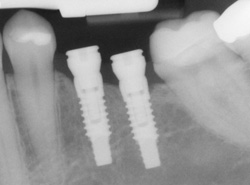

Implants

If you have missing teeth, it is crucial to replace them. Without all your teeth, chewing and eating can destabilize your bite and cause you discomfort. When teeth are missing, your mouth can shift and even cause your face to look older. Implants are a great way to replace your missing teeth.

An implant is a new tooth made of steel and porcelain that looks just like your natural tooth. Your implant is composed of two parts that mimic a tooth's root and crown. The implant's "root" is a titanium steel rod placed into the jaw bone to act as a root. Once the rod is in place, a porcelain crown is attached to replace the top part of your tooth.

Implants may also be used to anchor dentures, especially lower dentures that tend to shift when you talk or chew. Plus, for patients with removable partial dentures, implants can replace missing teeth so that you have a more natural-looking smile.